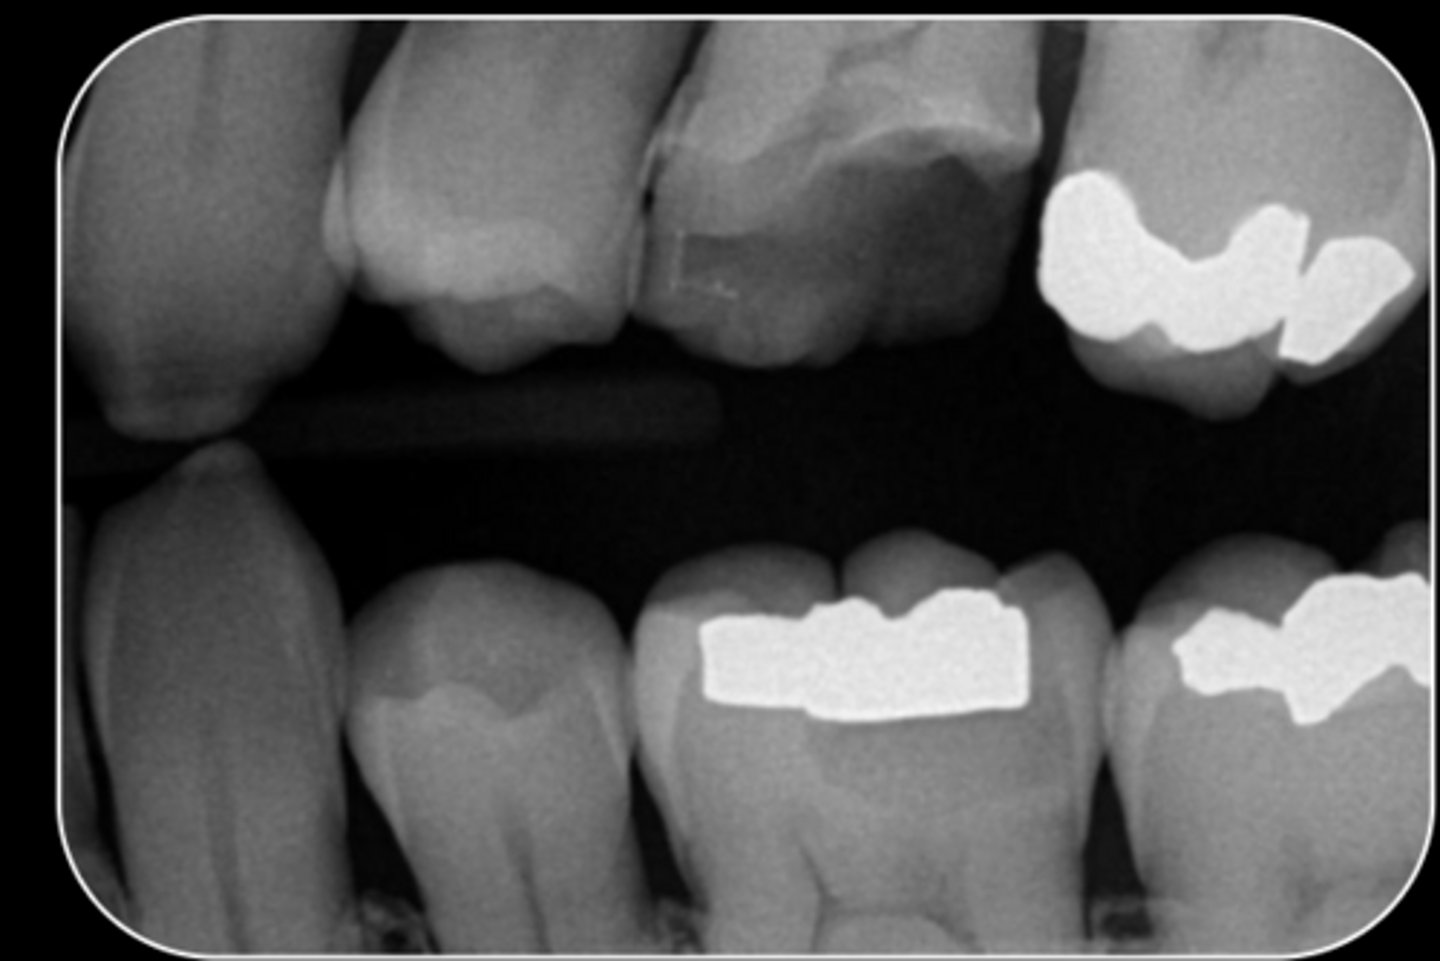

What are the radiographic findings on #3?

- M Caries

- Pulp stones

- Pulp chamber receeded

What are the radiographic findings on #14?

- Fracture Mesial-Distal

- Caries approximating pulp chamber